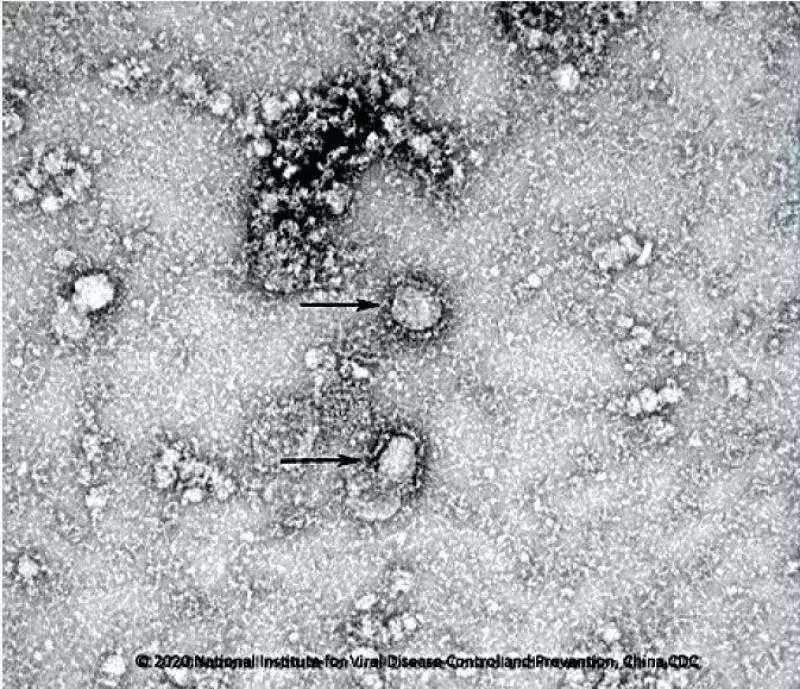

新型冠状病毒 (SARS-CoV-2)是一种于2019年年底被发现的新型冠状病毒,属于有包膜的RNA病毒家族。这一家族病毒包括中东呼吸综合征(MERS)病毒和严重急性呼吸综合征(SARS)病毒,它们均可引发人类呼吸系统的严重感染。该病毒导致了新型冠状病毒肺炎,该疾病此前从未在人体内发现。截至2020年2月21日,该病毒已导致超过七万五千人感染,两千一百多人死亡。目前新型冠状病毒疫情已被世界卫生组织(WHO)列为“国际关注的突发公共卫生事件”。针对新型冠状病毒目前尚无预防性疫苗。

“S-三聚体”是一种新型冠状病毒表面抗原S蛋白三聚物亚单位候选疫苗。与艾滋病毒, 呼吸道合胞病毒及流感病毒等其他包膜RNA病毒类似,SARS-CoV-2也是RNA病毒,其表面抗原S蛋白也具有三聚体结构,病毒通过其三聚体抗原(S蛋白)与宿主细胞表面ACE2受体结合,从而进入人体细胞,使其成为疫苗开发的主要目标抗原。“S-三聚体”类似于天然三聚体病毒表面蛋白,并可通过哺乳动物细胞培养进行快速表达 。